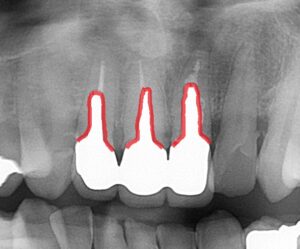

エックス線(レントゲン写真)です。

今回治療した前歯3本ですが、レントゲンで白く写っている

金属の心棒が太く長く差し込まれています。

メタルコアは金属で折れることがありません。

差し込んである歯は柔らかく、金属の心棒に負担をかけると歯が割れてしまいます。

実際に「歯根破折」は差し歯にしてある歯に多く、歯が割れたという方の理由の主な原因にもなっています。

歯が割れると、歯根破折といって歯を抜歯しなくてはいけません。

そのため太く長いコアが入っていると担当医から治療の断念を告げられることもあります。